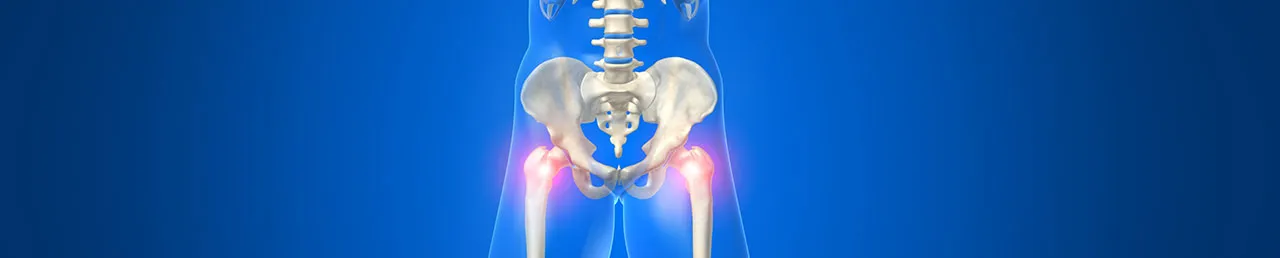

고관절은 골반의 관골구와 대퇴골두를 연결하는 관절입니다. 골반과 다리가 만나는 지점에 위치하며 체중을 지탱하고 다리의 움직임을 가능하게 합니다.

고관절은 특히 뼈 조직이 약해지는 60세 이후에 침대에서 미끄러지거나 넘어지는 등 사소한 충격에도 쉽게 손상되기 쉽습니다. 평균 수명이 증가함에 따라 고관절 골절의 빈도도 늘고 있습니다. 고관절 골절은 대퇴골의 목 부위가 골절되는 대퇴 경부 골절과 목 아래 부위가 골절되는 대퇴골간 골절로 나눌 수 있습니다. 노인에게는 잦은 낙상으로 인해 대퇴골간 골절이 더 흔하게 발생합니다.

고관절 수술은 손상 정도에 따라 전치환술과 반치환술로 나뉩니다.